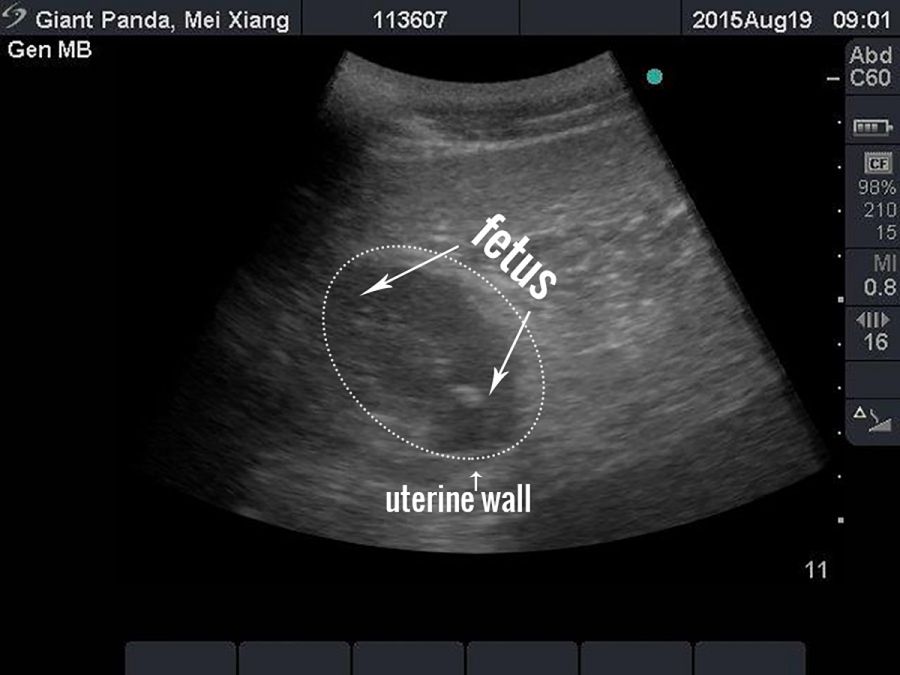

La madre fue inseminada el 26 de abril y la primera vez que se detectó un feto en una ecografía fue el 19 de agosto.

Ecografía donde se ve a uno de los fetos

Ecografía donde se ve a uno de los fetos AFP Handout